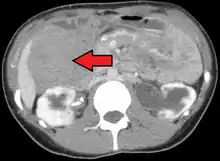

| Desmoid tumor as seen on CT scan | |

MRI or CT imaging scans are commonly used for monitoring.[45][1]